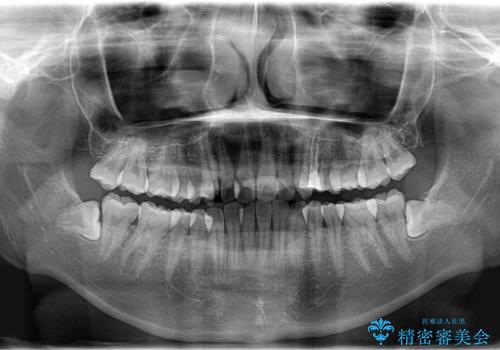

ハーフリンガル矯正 抜歯をして前歯を下げる

- 上顎の両側第1小臼歯抜歯による抜歯矯正を計画した。

上顎の抜歯により上の前歯の位置を大幅に後ろに下げることができます。

奥歯の位置関係など、様々な要素を加味し、適応を判断する必要があります。